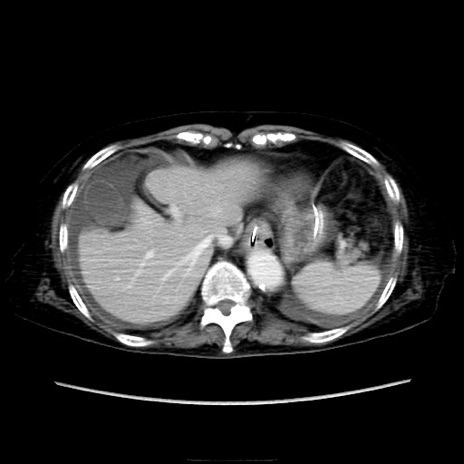

症例40(横断像)

【症例】90歳代女性

【主訴】腹痛・嘔吐

【現病歴】 食欲低下、嘔吐があり昨日他院受診。肺炎と診断され入院となる。入院後より腹部全体に圧痛あり。胃管留置され経過みていたが、症状持続するため、

当院転院となる。

【既往歴】胸椎圧迫骨折、胆石症

【身体所見】腹部:中央に激痛あり、圧痛あり、反跳痛不明

【データ】WBC 17100、CRP 18.82

横断像